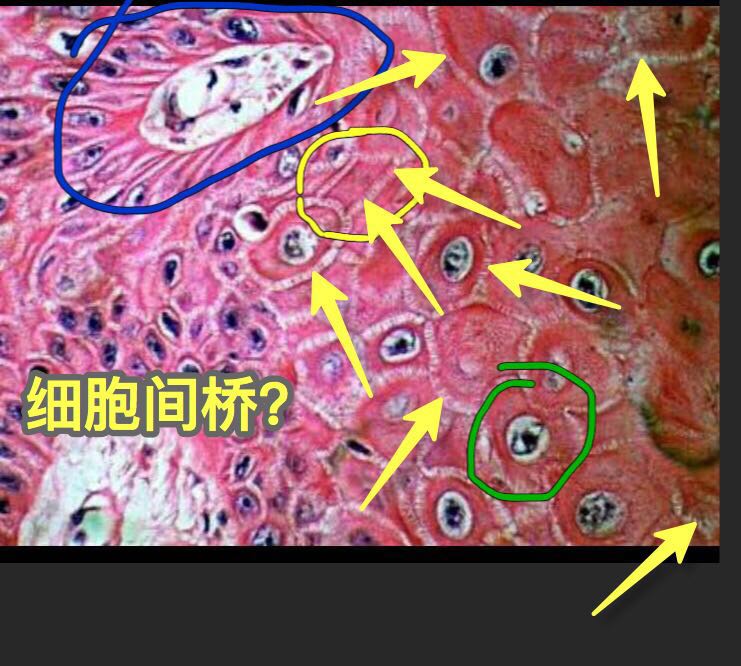

连晓峰:细胞间桥我理解为鳞状细胞之间像小梯子一样的结构,把各个鳞状细胞之间连接起来,鳞癌恶性程度越高,细胞间桥越少。有时候细胞形态不好区分,又没有角化珠,就得看细胞间桥来鉴别。不知道是不是这样理解,王老师@王兆宇 细胞间桥是鳞状细胞️高分化鳞癌、角化型鳞癌的特有结构吗?其它组织都没有吗? 王娟红:高分化,中分化鳞癌有,其他无,是鳞癌特有的

高分化,中分化鳞癌有,其他无,是鳞癌特有的